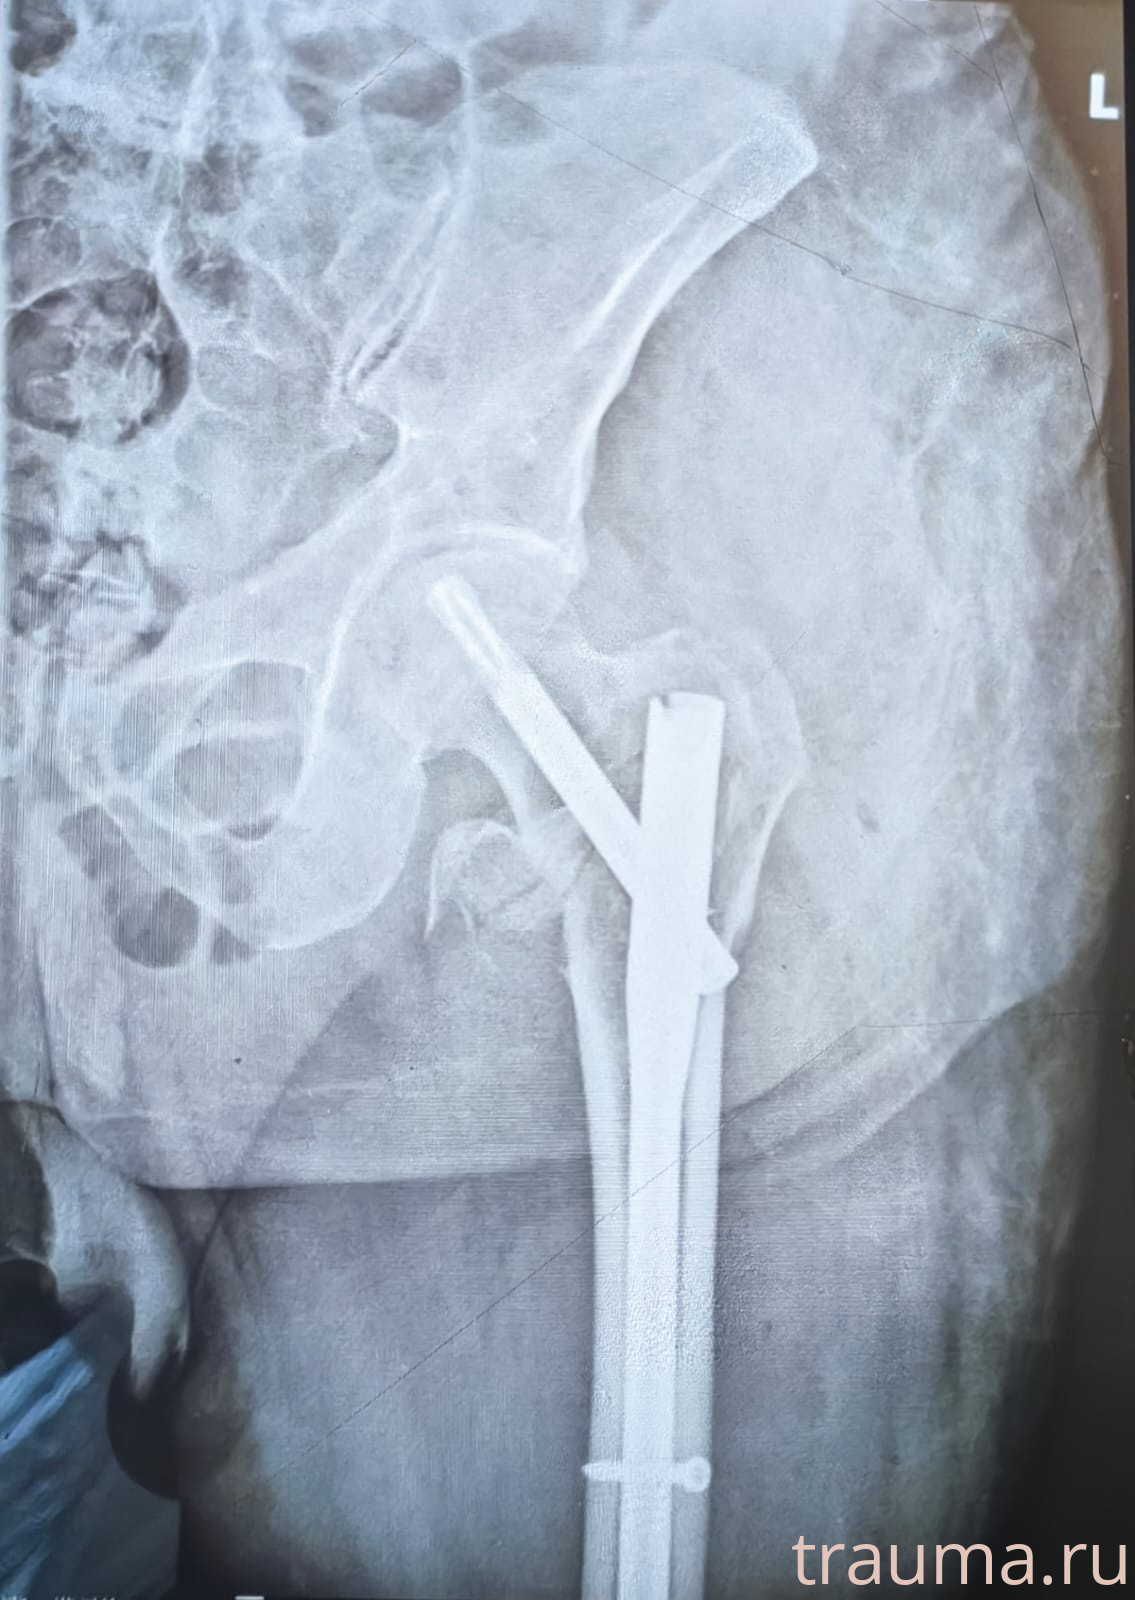

Рентген на дому: по вашему адресу приезжает врач-рентгенолог, травматолог-ортопед с мобильным рентгеновским аппаратом, проводит диагностику травмы или заболевания, делает необходимые рентгенограммы, дает рекомендации по дальнейшему лечению. Получить качественные снимки в домашних условиях возможно благодаря уникальной методике, разработанной МосРентген Центром для института  Склифосовского